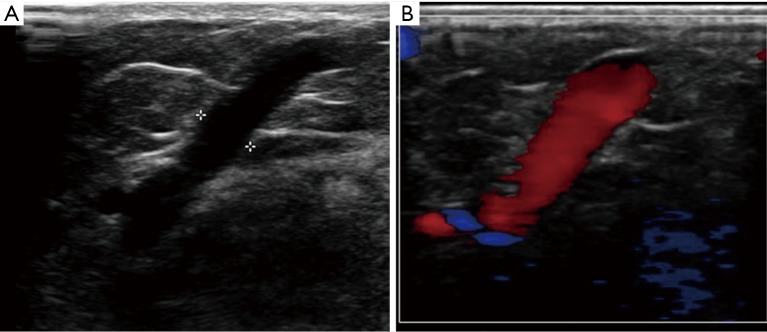

Figure 1.

Insufficient leg perforator. (A) An isolated abnormally dilated perforator at inferior thigh level with accompanying local skin discoloration without any superficial dilated or insufficient veins; (B) color Doppler ultrasound (US) shows the refluxing vein has reverse flow from deep system to superficial vein for more than 5 secs, with diameter more than 3.5 mm.